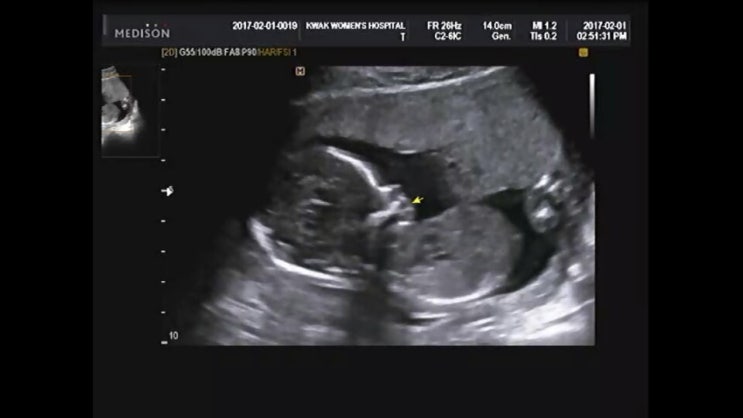

[임신20주차] 무럭무럭 자라는 비단이

| 임신 20주차, 무럭무럭 자라는 비단 정신없이 일상을 보내다보니 비단이도 20주차에 접어들게 되었다. ...